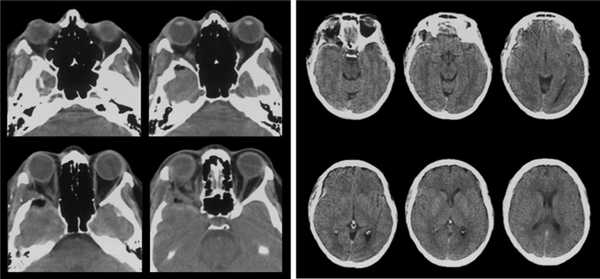

В раннем послеоперационном периоде выполнена КТ головного мозга и орбит, по результатам которой остаточной опухолевой ткани не определяется (рис. 5).

Рисунок 5. КТ орбит в раннем послеоперационном периоде. Визуализируются послеоперационные изменения в глазнице, остаточной опухолевой ткани нет.